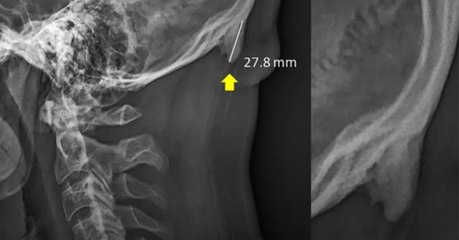

Cette ''femme licorne'' a une étrange protubérance qui pousse sur son crâne